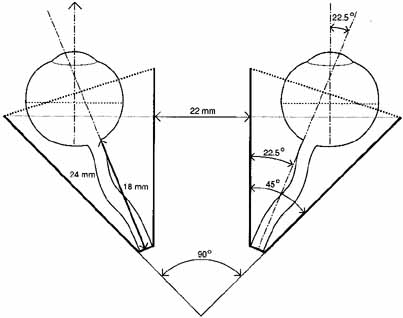

levator aponeurosis recession.43 The Globe The globe is located in the anterior orbit situated slightly superiorly

and laterally. The superior, medial, and inferior orbital rims extend

anteriorly to be on about the same frontal plane as the front of the

eye. The lateral rim is recessed 12 to 18 mm behind the cornea as measured

by exophthalmometry. Attached to the eye are the six extraocular

muscles, the optic nerve, the long and short posterior ciliary nerves, the

anterior and posterior ciliary arteries, and the vortex veins (Fig. 17). The globe is covered behind the corneal limbus by Tenon's

fascia and is supported in the orbit by Lockwood's ligament. The

average volume of the eye is about 6.5 cc compared to the orbital volume, which

is about 29.7 cc.2 The shape is not truly spheric; rather it is formed by the union of two

spheres, being that of the cornea and the sclera, with radius of curvatures

The average adult and newborn infant globe dimensions are given in Table 2.

TABLE 2. Average Globe Dimensions

| Adult | |

| Anterior-posterior | 24 mm |

| Vertical | 23 mm |

| Horizontal | 23.5 mm |

| Newborn Infant | |

| Anterior-posterior | 16.4 mm |

| Vertical | 16 mm |

| Horizontal | 15.4 mm | Orbital Nerves Entering the orbit are the optic (cranial nerve II), the oculomotor (cranial